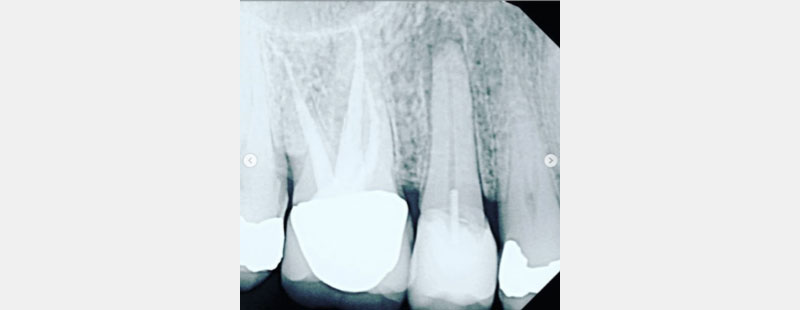

A recent PA, with the BW you might already have, will provide essential information about that tooth. Are the pulp chambers uniform and evident? Can you see the pulp chambers? Are they grey? Or are they sandwiched and shrunken (aka calcifying or calcified)?

Can you cold test the tooth? If calcified, it might not respond to cold, so how do you assess? Is the cold response the same intensity as all the other teeth? Can you percuss the tooth? Is it different in how it feels versus the adjacent teeth or virgin nearby teeth (if applicable)? If not, can you suggest an endodontic consultation?

In Scenario 3, pulpal necrosis (likely present prior to crown cementation) progressed, resulting in facial swelling. However, each scenario could have likely been avoided with the suggested limited testing in conjunction with a PA film and an endodontic consultation.

As a side note, it usually takes approximately three months for radiographic changes of pulpal necrosis to become evident with a periapical lucency. Please remember these lucencies aren’t always evident.

In Figs. 7–9, each patient was asymptomatic, but clearly all had medium- to large-sized restorations.